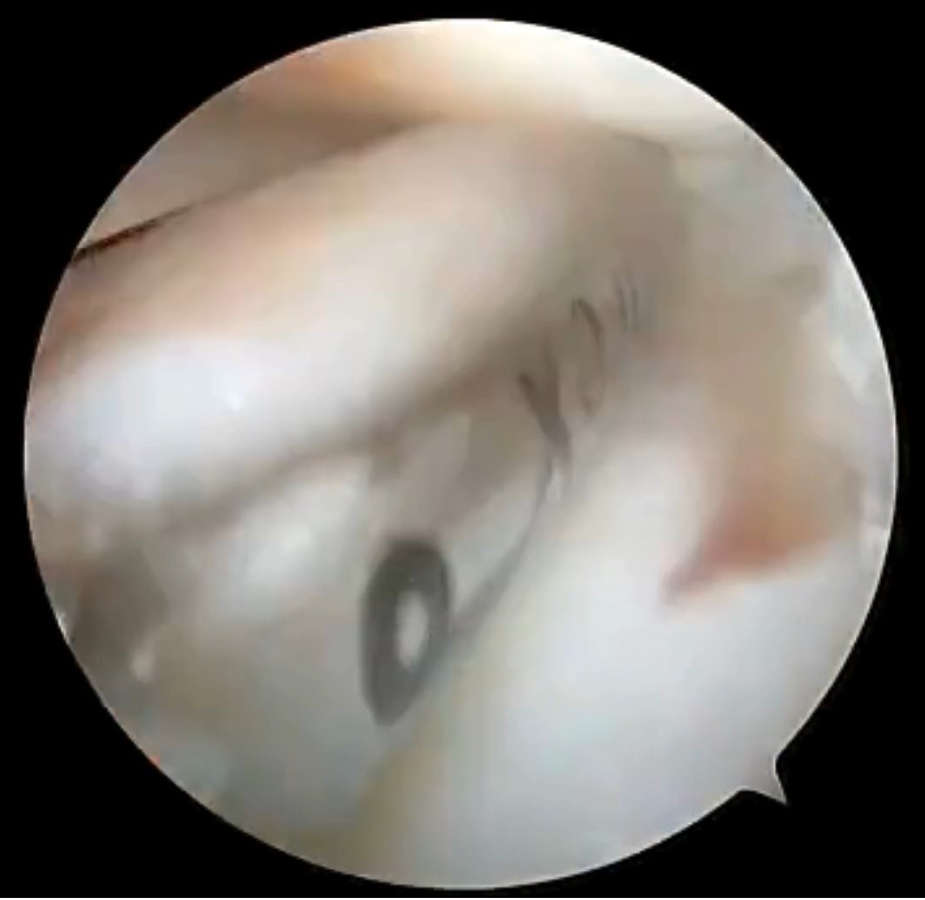

A complete tear of the CCL was noted, and an arthroscopic shaver was used to debride the torn fibers (Figure 2). To evaluate the medial meniscus, valgus stress was placed on the limb, and the arthroscope was directed medially. A bucket handle tear of the meniscus was identified (Figure 3). The bucket handle tear is released via transection with an arthroscopic punch, and the abaxial portion of the tear is debrided (Figure 4). The axial portion of the tear (the meniscotibial ligament) is subsequently debrided to remove the entirety of the tear (Figure 5). Following meniscectomy, the caudal aspect of the medial compartment of the joint is probed thoroughly to interrogate for additional bucket handle tears (Figure 6).

Figure 2

Figure 3

The medial femoral condyle is at the top of the image, the cranial horn of the medial meniscus is at the bottom left of the image. An arthroscopic probe can be seen underneath the bucket handle tear of the caudal pole of the meniscus, retracting the torn portion of meniscus cranially. Note the significant number of frayed fibers that are typically indicative of chronicity.

Figure 4

Figure 5

Figure 6